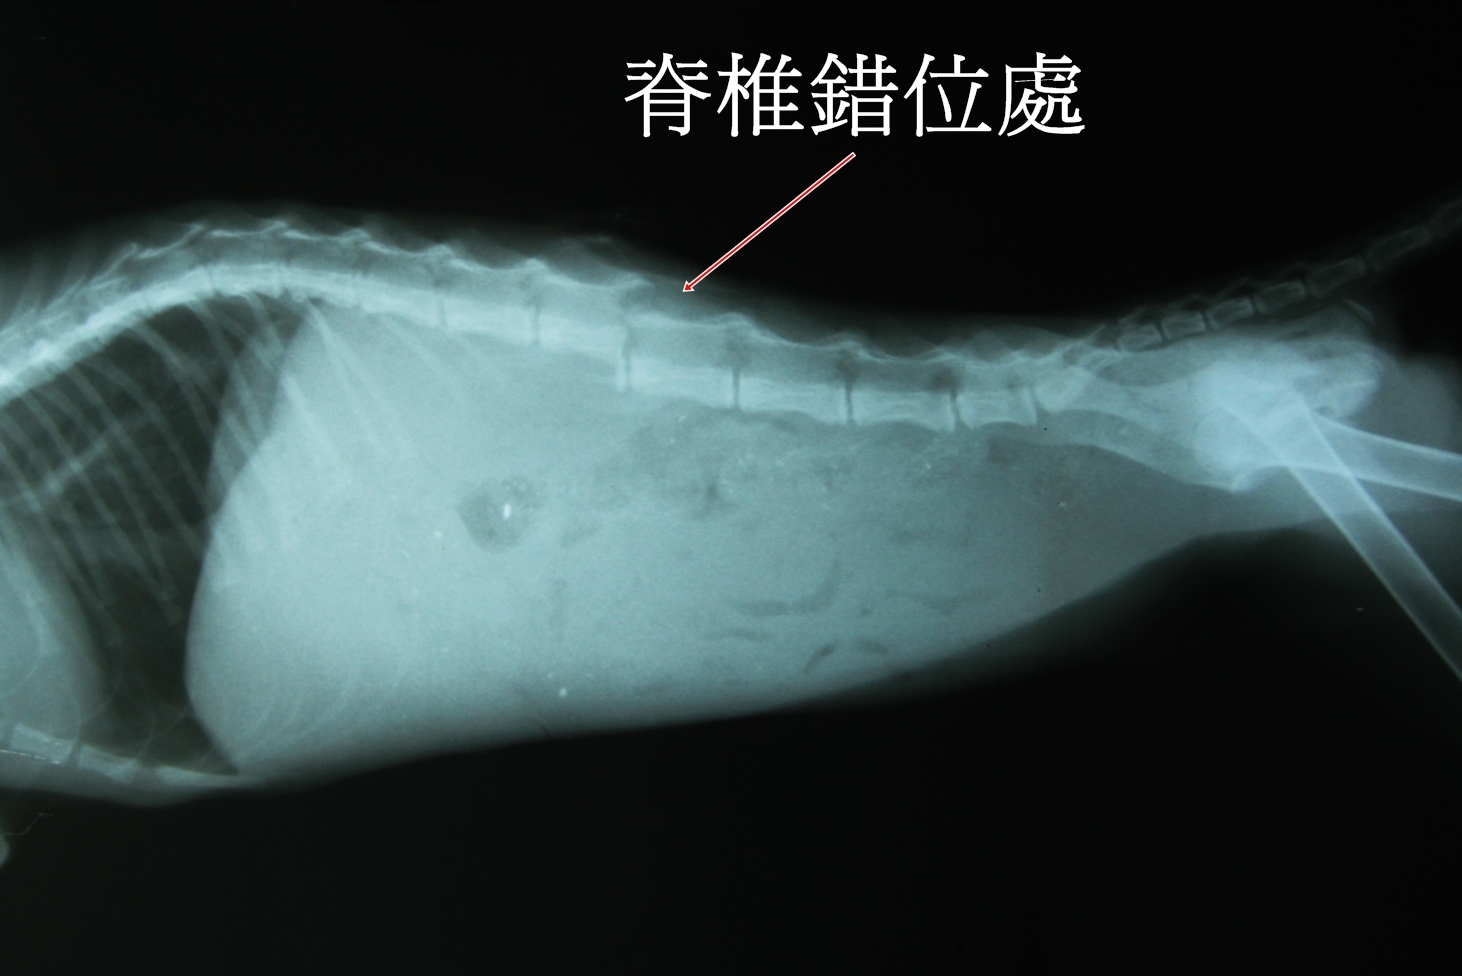

在X光的顯示下,發現小將的脊椎錯位,下半身雖然冰涼但有輕微的痛覺反應,醫生說,有成功再站起的機率,可以努力看看。短短的一句話卻讓我思考了好久,因為,如果他手術後依舊癱瘓,貓咪不但一輩子陷入無法爬起的痛苦中,而且可能還需人工擠尿和擠便,重要的是,原發現的愛心姐姐無法收容他,未來的他該何去何從?

為了讓小將術後能達到最佳狀態,由擅長外科手術聯合醫院的黃醫師來執行,目前恢復情況良好,小將也在大家的期待中自行站立了起來。